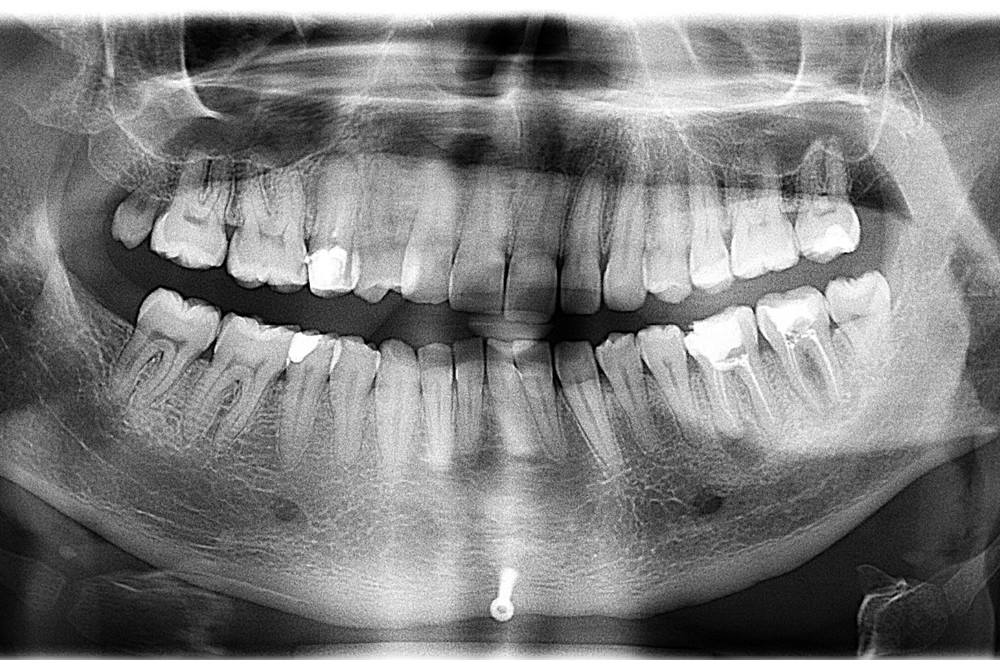

Но мы отвлеклись. Вот снимок пациентки после лечения.

Кроме зубов "мудрости" не удалено ничего. Тут проведено лечение корневых каналов, вкладки, коронки. Какие удаленные 22 зуба? Это бред СМИ, нацеленный на непонятную травлю. Конечно, кого заинтересует новость "пациентке не понравился результат лечения и она подала в суд", фу, уныло. А вот "шок!!врачи-убийцы рядом!! Схватили, выдрали 22 здоровых зуба!!и вкатали счет на миллион!!не допустим врачебного произвола!!!111" - вот это уже вызывает подрыв у очень многих.